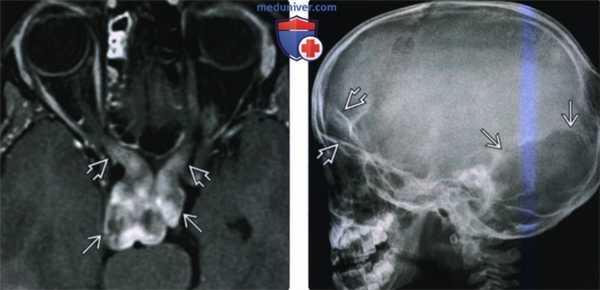

(Слева) При аксиальной МРТ (Т1ВИ С+) у ребенка с НФ1 визуализируется большая глиома зрительных путей, вовлекающая хиазму и прехиазмальную часть зрительных нервов.

(Справа) На рентгенограмме в боковой проекции у ребенка с ПНФ основания черепа визуализируется большой дефект лямбовидного шва, типичное, но редкое изменение у детей с НФ1. Обратите внимание на асимметрию крыши глазниц, обусловлено поражением глазницы с одной стороны, типичным для пациентов с дисплазией крыла клиновидной кости и ПНФ.